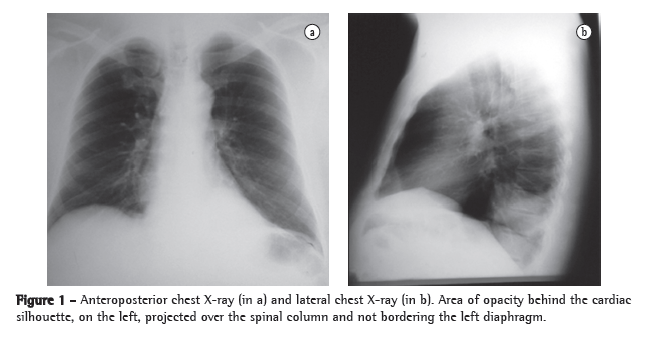

Physical examination revealed good general health, no fever, an HR of 88 bpm and an arterial pressure of 90-145 mmHg. The cardiac auscultation was normal, and examination of the lung revealed reduced expansion and diminished breath sounds in the lower third of the left hemithorax, as well as dullness to percussion in this same region. The rest of the physical examination revealed no abnormalities. The results of the laboratory tests performed at admission, such as blood workup, lipid profile, coagulation profile, determination of electrolyte concentrations, renal function test and hepatic function test, were normal. The ESR was 32 mm/h. Serology for HIV was negative. A chest X-ray at admission revealed opacity in the posterior segment of the left lower lobe (Figure 1). A CT scan of the chest with two-dimensional reconstruction revealed an aortic branch directed toward the pulmonary opacity (Figure 2), which is consistent with a diagnosis of pulmonary sequestration. The patient was referred for surgery, and a left lower lobectomy was performed to resect the anomalous pulmonary tissue (Figure 3). After the macroscopic analysis of the surgical sample, the patient was diagnosed with intralobar sequestration. The postoperative evolution was favorable, and the patient was discharged to outpatient treatment.

When faced with a 56-year-old patient, admitted for investigation of hemoptysis, with no clinical evidence of respiratory infection, with no history of smoking and having an area of opacity in the posterior segment of the left lower lobe on chest X-ray, one of the hypotheses to be considered is that it is a case of pulmonary sequestration.